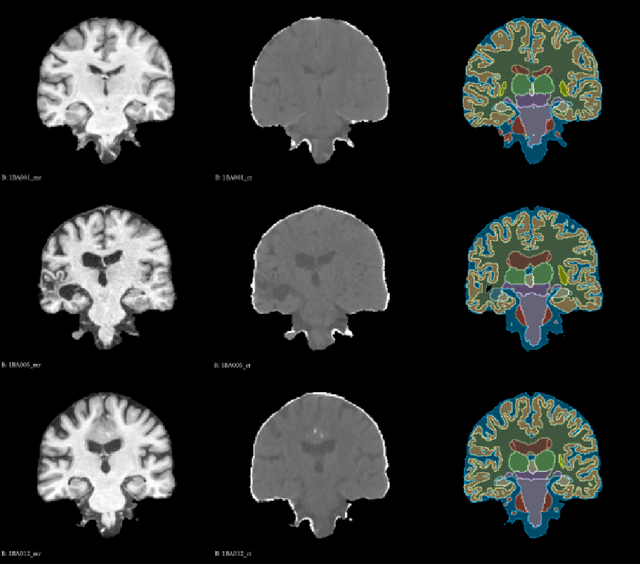

Abstract:Image registration, a critical process in medical imaging, involves aligning different sets of medical imaging data into a single unified coordinate system. Deep learning networks, such as the Convolutional Neural Network (CNN)-based VoxelMorph, Vision Transformer (ViT)-based TransMorph, and State Space Model (SSM)-based MambaMorph, have demonstrated effective performance in this domain. The recent Visual State Space Model (VMamba), which incorporates a cross-scan module with SSM, has exhibited promising improvements in modeling global-range dependencies with efficient computational cost in computer vision tasks. This paper hereby introduces an exploration of VMamba with image registration, named VMambaMorph. This novel hybrid VMamba-CNN network is designed specifically for 3D image registration. Utilizing a U-shaped network architecture, VMambaMorph computes the deformation field based on target and source volumes. The VMamba-based block with 2D cross-scan module is redesigned for 3D volumetric feature processing. To overcome the complex motion and structure on multi-modality images, we further propose a fine-tune recursive registration framework. We validate VMambaMorph using a public benchmark brain MR-CT registration dataset, comparing its performance against current state-of-the-art methods. The results indicate that VMambaMorph achieves competitive registration quality. The code for VMambaMorph with all baseline methods is available on GitHub.

Abstract:Deformable image registration is an essential approach for medical image analysis.This paper introduces MambaMorph, an innovative multi-modality deformable registration network, specifically designed for Magnetic Resonance (MR) and Computed Tomography (CT) image alignment. MambaMorph stands out with its Mamba-based registration module and a contrastive feature learning approach, addressing the prevalent challenges in multi-modality registration. The network leverages Mamba blocks for efficient long-range modeling and high-dimensional data processing, coupled with a feature extractor that learns fine-grained features for enhanced registration accuracy. Experimental results showcase MambaMorph's superior performance over existing methods in MR-CT registration, underlining its potential in clinical applications. This work underscores the significance of feature learning in multi-modality registration and positions MambaMorph as a trailblazing solution in this field. The code for MambaMorph is available at: https://github.com/Guo-Stone/MambaMorph.